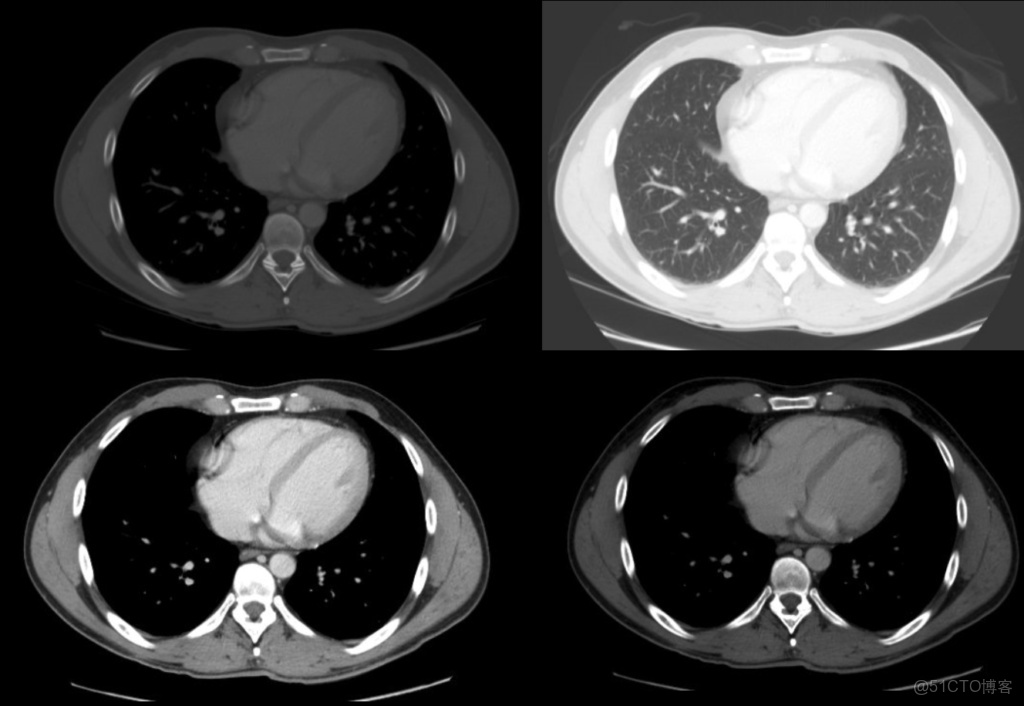

肺窗口窗口設置: (W:1600,L:-600)或(W:1500,L:-500)優點: 顧名思義,此窗口用於評估肺。靠近肺組織密度的高窗口水平(鑑於其低密度水平為低),並與寬窗口一起使用以提供良好的分辨率並可視化胸部的各種密度,例如肺實質以及相鄰的血管。

CLAHE算法增強局部對比度的X光圖像增強效果對比_#python 計算對比度_10

肺窗有助於評價肺,某些胸部病理學(如特定類型的結節)只能在這個窗口上看到。